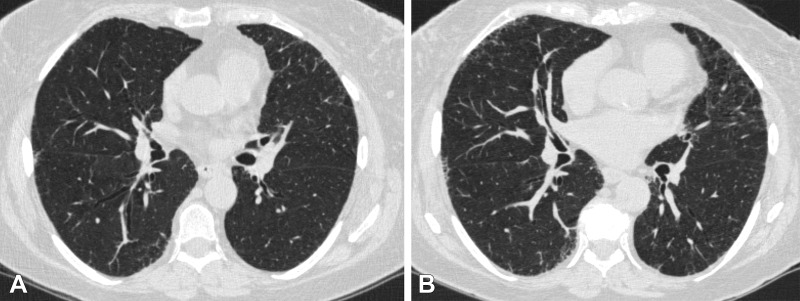

Figure 2:

Axial chest CT scans (0.75-mm section thickness, reconstructed with b31f kernel; Siemens Medical Solutions) at (A) visit 1 and (B) visit 2 at the level of the takeoff of the right middle bronchus of a participant with 1.2 annual percentage quantitative interstitial abnormality progression. The female participant was 62 years old at visit 1 and 67 years old at visit 2 and a current smoker at both visits, with a 47.5 pack-year history at visit 2. This participant had four subsequent acute respiratory disease (ARD) events and three subsequent severe ARD events.